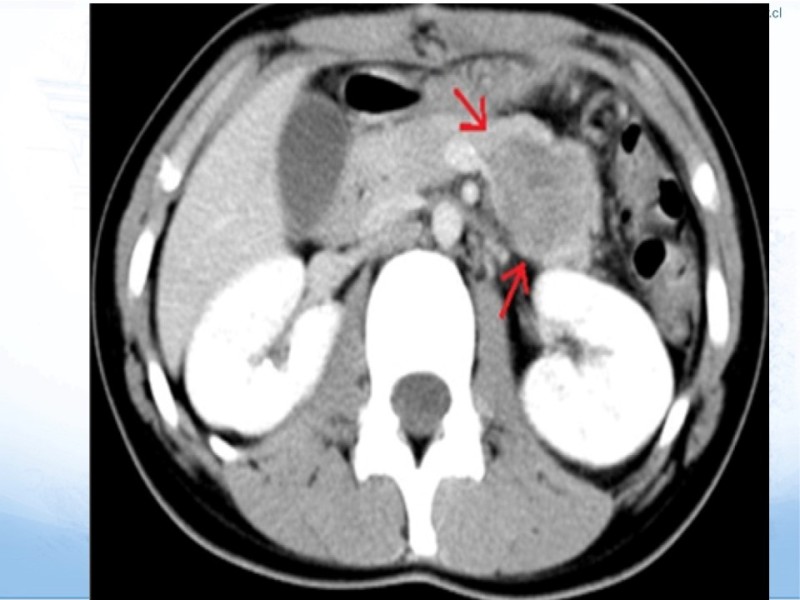

Tumores Pancreáticos no adenocarcinomas

Hepatobiliopancreático

| Autor: Dr. Matías Osorio Reyes